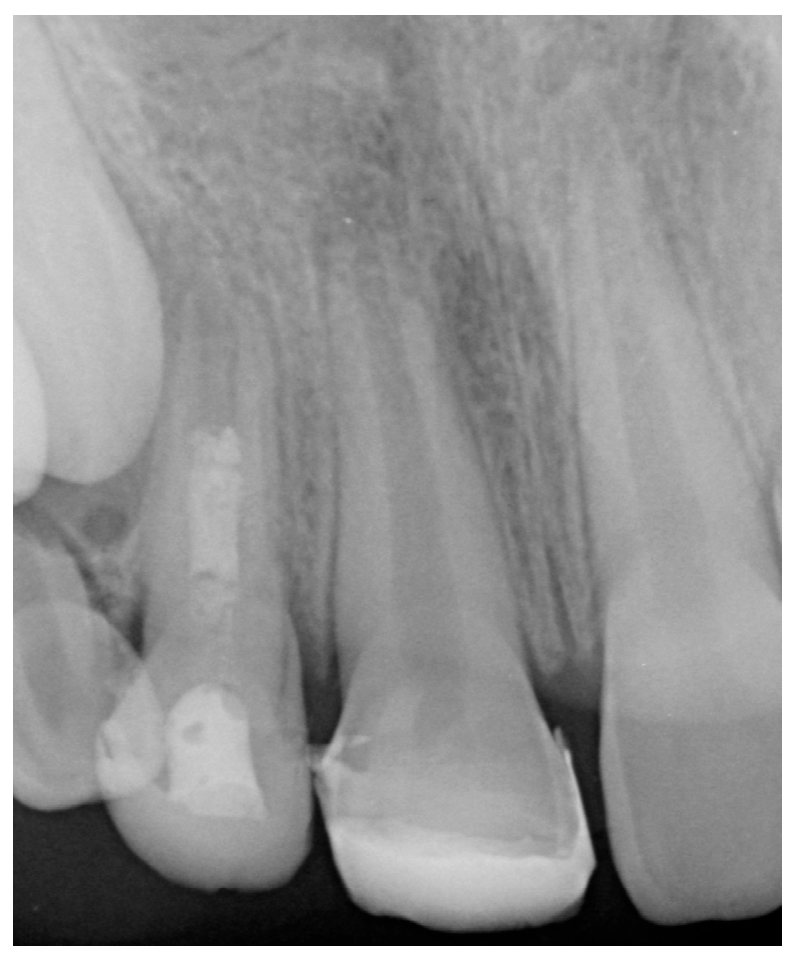

| TEETH | Irrigation Protocol | Intracanal Medication | Biomaterial | Apex Measurement (mm) Before Treatment | Apex Measurement (mm) After Treatment | Type of Apical Closure | |

|---|---|---|---|---|---|---|---|

| Case 1 | 12 | 17% EDTA NaOCl | TAP | MTA | 3.7 mm | 2.2 mm | Calcified apical barrier |

| Case 2 | 11/21 | 17% EDTA NaOCl | Ca(OH)2 | BIODENTINE® | 3.1 mm/2.8 mm | 2.3 mm/2 mm | Calcified apical barrier |